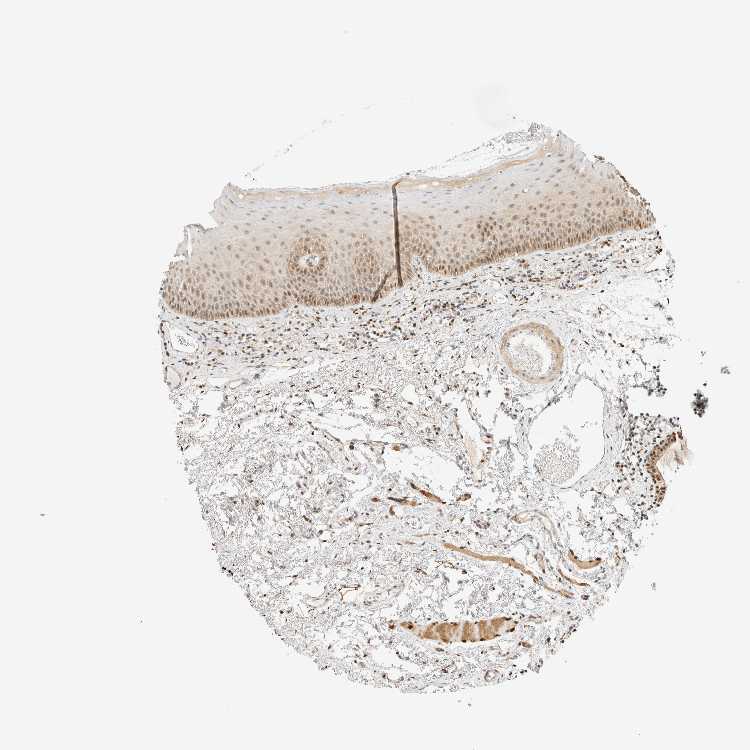

TISSUE PRIMARY DATA ORAL MUCOSA Show tissue menu

ORAL MUCOSA - Antibody stainingi

Antibody staining in the annotated cell types in the current human tissue is reported as not detected, low, medium, or high, based on conventional immunohistochemistry profiling in selected tissues. This score is based on the combination of the staining intensity and fraction of stained cells.

Each image is clickable and will lead to virtual microscopy that enables deeper exploration of all samples and also displays staining intensity scores, fraction scores and subcellular localization as well as patient and tissue information for each sample.

Antibody HPA023438

Squamous epithelial cells Medium